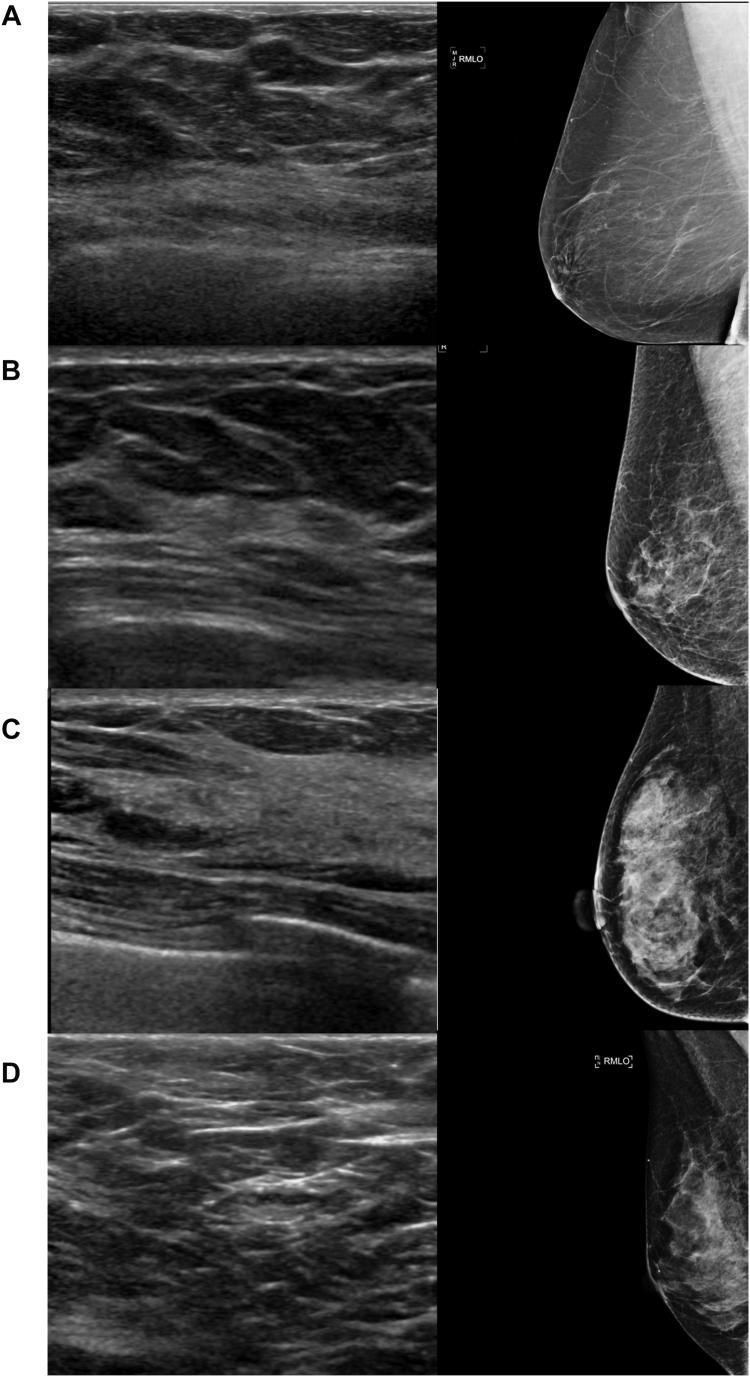

Breast density, as derived from mammographic images and defined by the Breast Imaging Reporting & Data System (BI-RADS), is one of the strongest risk factors for breast cancer. Breast ultrasound is an alternative breast cancer screening modality, particularly useful in low-resource, rural contexts. To date, breast ultrasound has not been used to inform risk models that need breast density. The purpose of this study is to explore the use of artificial intelligence (AI) to predict BI-RADS breast density category from clinical breast ultrasound imaging.

METHODS

乳腺密度源自乳腺钼靶图像,由乳腺影像报告和数据系统(BI-RADS)定义,是乳腺癌最强的风险因素之一。乳腺超声是另一种乳腺癌筛查方式,在资源匮乏的农村地区尤为有用。迄今为止,乳腺超声尚未用于需要乳腺密度的风险模型。本研究的目的是探索使用人工智能(AI)从临床乳腺超声成像预测BI-RADS乳腺密度类别。

方法